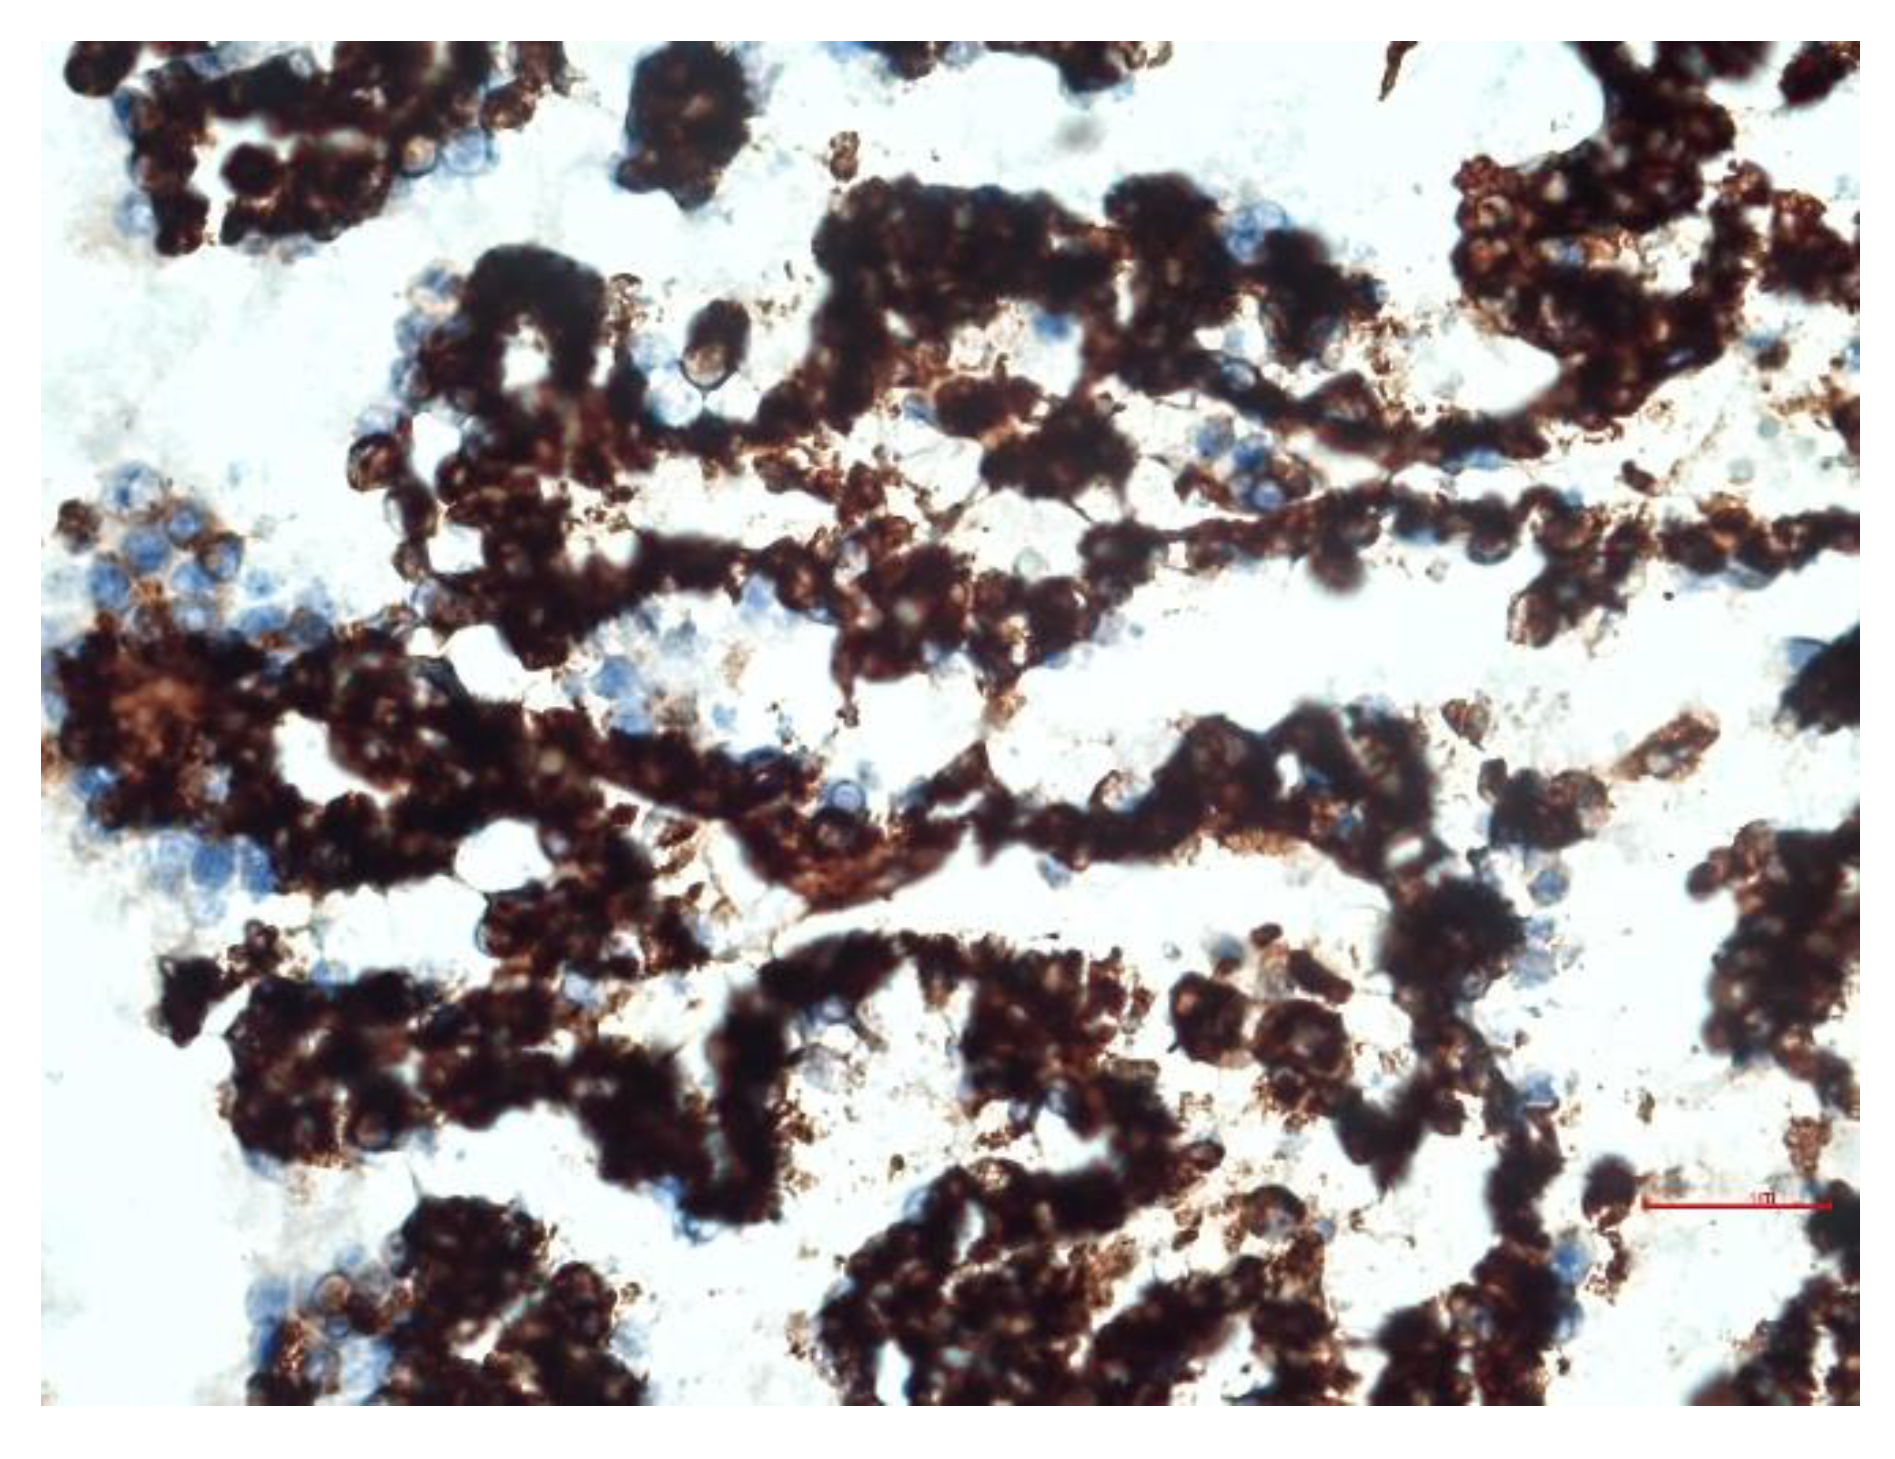

3.4. Immunohistochemical Aspects